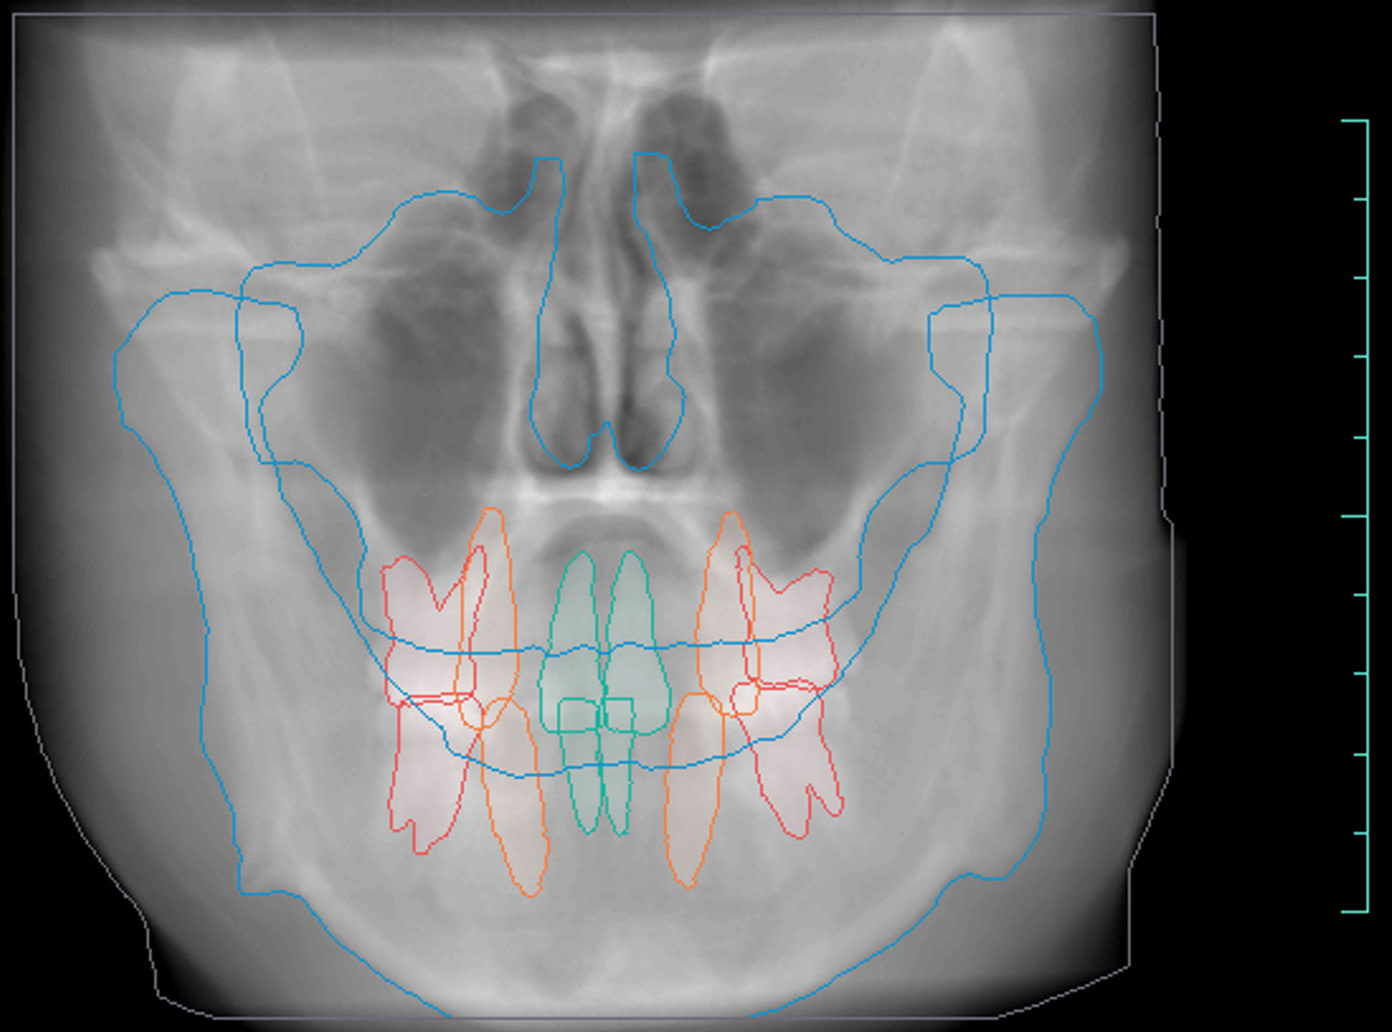

Orthodontic Report

Diagnocat is also capable of generating orthodontic reports.

This requires a CBCT radiograph with a minimum field of view of 13 x 15 x 15cm. Our Kavo OP3D machine achieves this by taking a double-field exposure and stacking two exposures on top of each other.

Diagnocat generates OPG and frontal and lateral cephalometric reconstructions from the CBCT data.

Tracings of the maxilla, mandible, central incisors, canines and molars. All automatically.

Cross-sectional and coronal views of teeth show torque and buccolingual relationships such as crossbite.

TMJ coronal/sagittal slices and summations visualize abnormal positioning/shape of the mandibular condyle.

Orthodontic, endodontic, and implantology reports are basic, with room for useful extra details.

The orthodontic report generates OPG and front/lateral cephalograms. These are not as sharp as true OPG and cephalograms. Tracings of the maxilla, mandible, central incisors, canines, and molars are automatically produced on the generated frontal/lateral cephalogram.

I showed the orthodontic report to an orthodontist colleague. She found the tracings to be fairly accurate compared to a real lateral cephalogram of the same patient. She did further tracings on the generated lateral ceph and advised it was difficult to visualize points such as Nasion, ANS, A Point, Condylion, and Orbitae and visualize the fourth vertebrae to determine peak growth phase. Furthermore, other orthodontic software can automatically calculate skeletal/dental relationships, planes, and angles.

The company did inform us that they are working on full functionality sets for orthodontic reports. This will come next year.